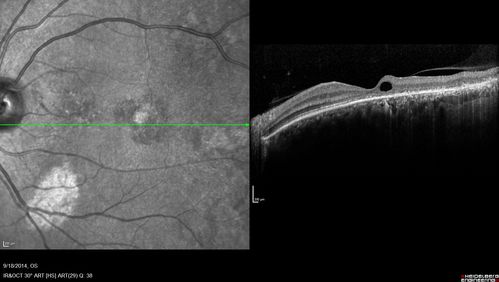

Chronic Central Serous Chorioretinopathy Both Eyes

60 year old man with 20 year history of chronic CSR. He has had laser and PDT in the past.  The left eye has been 20/100 for decades.  The right eye is now declining.  Was 20/32 and is down to 20/50.  There is chronic low grade subretinal fluid away from the center in the right eye.  (focal laser in the right eye in 2005, left eye 2001 at BPEI).  Refampin tried in 2012, Aldactone in 2013.  PDT in 204 and 2017  Images are from 2017